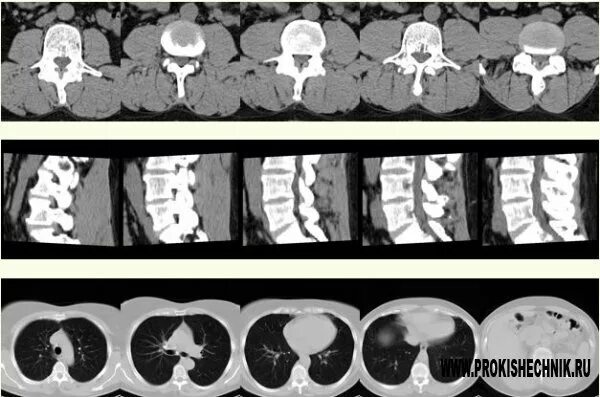

Что более информативно кт или мрт